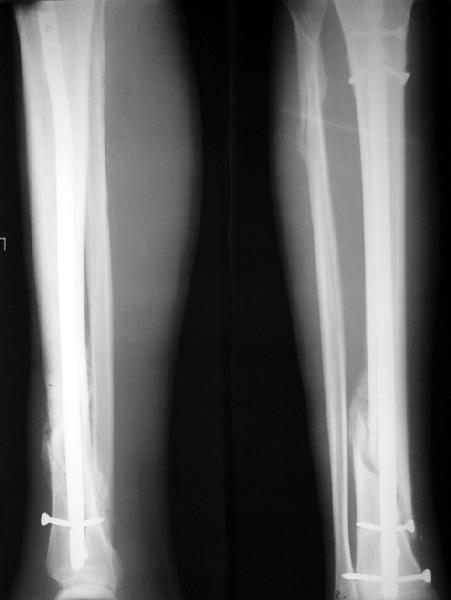

По крайней мере ходящих без дополнительной опоры через 1 месяц после операции с небольшой - при изолированной травме немало. Нестабильные по оси, кстати, не только оскольчатые, но и спиральные.

И если пациент еще не возвращается к полной нагрузке и функции, то не потому, что не разрешает врач, опасаясь несостоятельности фиксации.

Как мне показать пример? Фото стоящего на одной оперированной конечности пациента? O! Пример, подвигнувший нас на некоторое изменение технологий. Пациент этот ходил с полной нагрузкой вопреки рекомендациям. В качестве подтверждения - сломанный проксимальный статический винт к 1 мес., а к 2 мес. - все остальные. Сейчас мы перешли на более fool-proof остесинтез.

Это наглядная демонстрация возможности ранней полной нагрузки при нестабильном по оси повреждении, причем не в самых благоприятных механических условиях - при плохом сопоставлении, со слабым фиксатором.